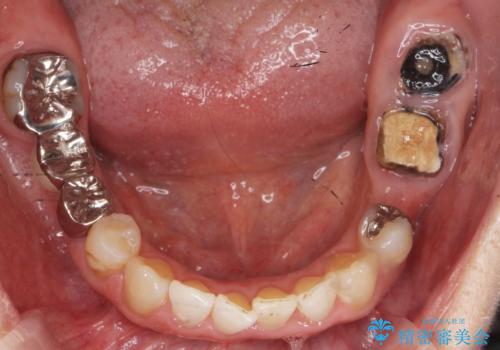

- 奥歯のブリッジの被せ物がとれてしまったとの主訴で来院された患者様です。

奥歯2本は虫歯により残っている健全歯質が少ないため、保存が難しい状態でした。

抜歯してインプラントを提案したところ、「どうしても抜きたくないので残してほしい」と強くご希望されました。

長期的な予後を保証できないことをご了承頂いた上で、歯根分割術、骨外科手術により歯の保存を試みました。

虫歯を丁寧に除去した後に歯根を分割し、骨を削合して健全歯質を露出させる骨外科手術を行いました。